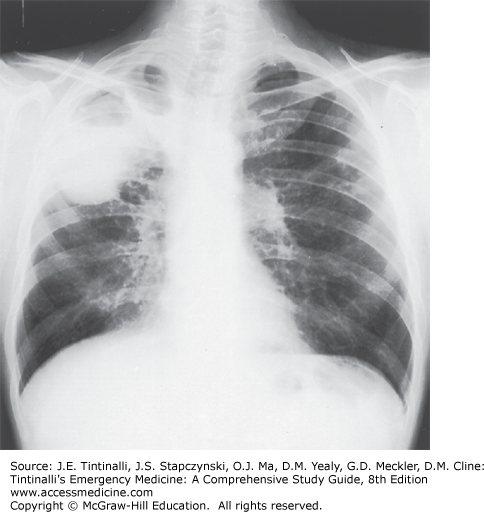

Cavitary Tuberculosis of the Right Upper Lobe on Chest Radiography

Cavitary tuberculosis of the right upper lobe.

Tintinalli JE, Stapczynski J, Ma O, Yealy DM, Meckler GD, Cline DM. Tintinalli’s Emergency Medicine: A Comprehensive Study Guide, 8e; 2016 Available at: https://accessmedicine.mhmedical.com/ViewLarge.aspx?figid=109429565&gbosContainerID=0&gbosid=0 Accessed: April 06, 2018